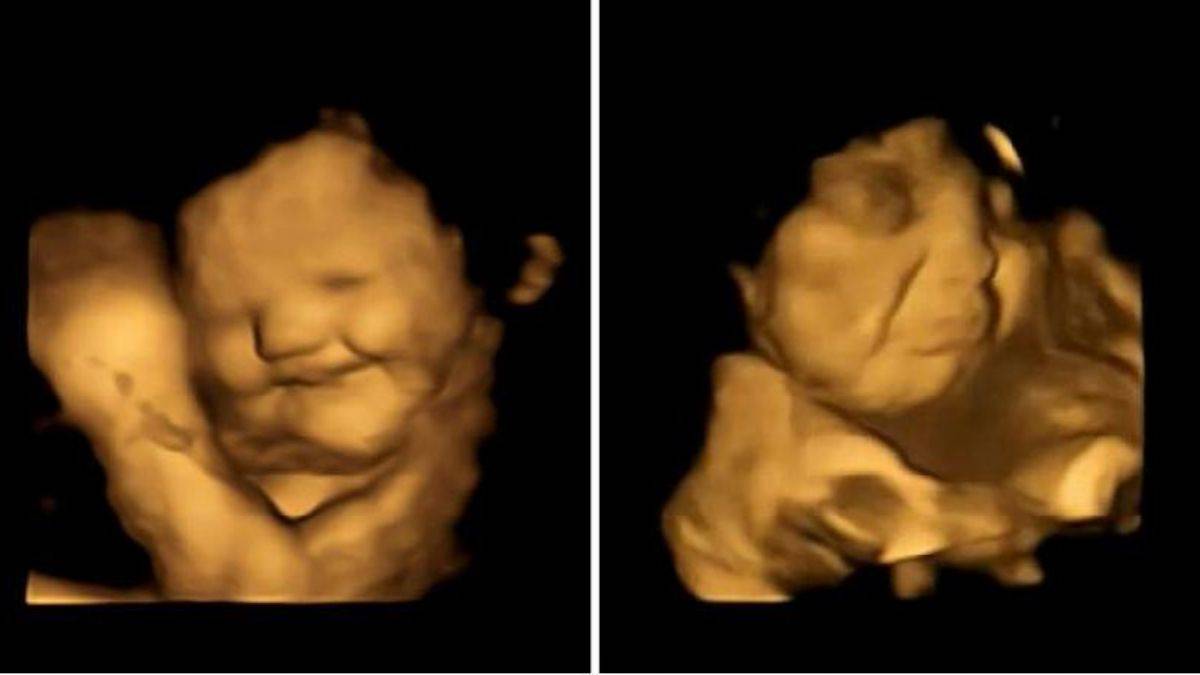

Yemeklerin ilk kez tadına bakan bebeklerin tepkileri şaşırttı

İngiltere’deki Durham Üniversitesi’nden araştırmacılar, henüz doğmamış bebeklerin ilk kez yemeğin tadına baktıklarında oluşan yüz ifadelerini yakaladılar. Henüz anne karnında olan bebeklerin havuçla karşılaştıklarında gülümsediklerini ve lahana geldiğinde de yüzlerini buruşturduklarını keşfettiler.

Times'ta yer alan habere göre, araştırma için 100 hamile kadından 400 mg havuç veya karalahana tozu içeren kapsülleri yutması istendi. Ultrason taramaları da doğmamış çocuklarının tepkilerini ortaya çıkardı. Araştırmacılar, anne tarafından yenen yiyeceklerdeki bileşiklerin kan dolaşımına geçtiğine ve plasenta yoluyla rahmin içindeki amniyotik sıvıya geçtiğine inanıyorlar.

Hoş bir havuç aromasına maruz kalanlar sürekli olarak daha fazla “gülme suratlı” tepkiler gösterirken, acı lahana daha fazla “ağlama suratına” yol açtı. Sonuçlar Psychological Science dergisinde yayınlandı.